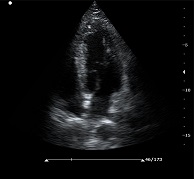

? ? ? ?C7為深圳安盛生物醫(yī)療技術(shù)有限公司新一代便攜式彩超產(chǎn)品,采用了先進(jìn)的PC平臺(tái),擁有強(qiáng)大的處理能力,優(yōu)異的圖像性能,集小巧輕便、全面的功能與輕巧流暢、特有的U型設(shè)計(jì)與一身,提供大眾新選擇。

? ?● 多種成像模式

? ? ? ?B、C、PW、CW、BCD三功、大角度偏轉(zhuǎn)成像、實(shí)時(shí)寬景成像、梯形成像(僅支持線(xiàn)陣)、解剖M型、彩色M型成像、組織多普勒成像、3D/4D成像